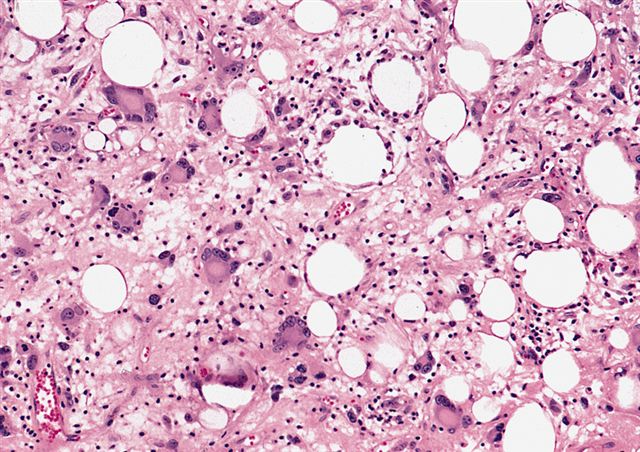

Microscopic (histologic) images

Contributed by Michael Clay, M.D., Melanie Bourgeau, M.D. and AFIP

Morphologic variability:

Metaplastic change:

- Inflammatory subtype

- Rare

- Almost always in the retroperitoneum where it is confused with nonlipogenic tumors

- Chronic inflammatory cells (B > T cells) with occasional lymphoid follicles scattered in a cellular fibrocollagenous stroma with sparse multinucleated atypical cells

- May obscure adipocytes

- Depends on subtype, generally composed of mature fat with variably sized adipocytes and bands of fibrotic stroma containing spindle cells with enlarged, hyperchromatic nuclei

- Can be markedly atypical

- Cellularity is low and mitotic figures are uncommon

- Atypical cells are more commonly found in fibrous septa and in a perivascular distribution